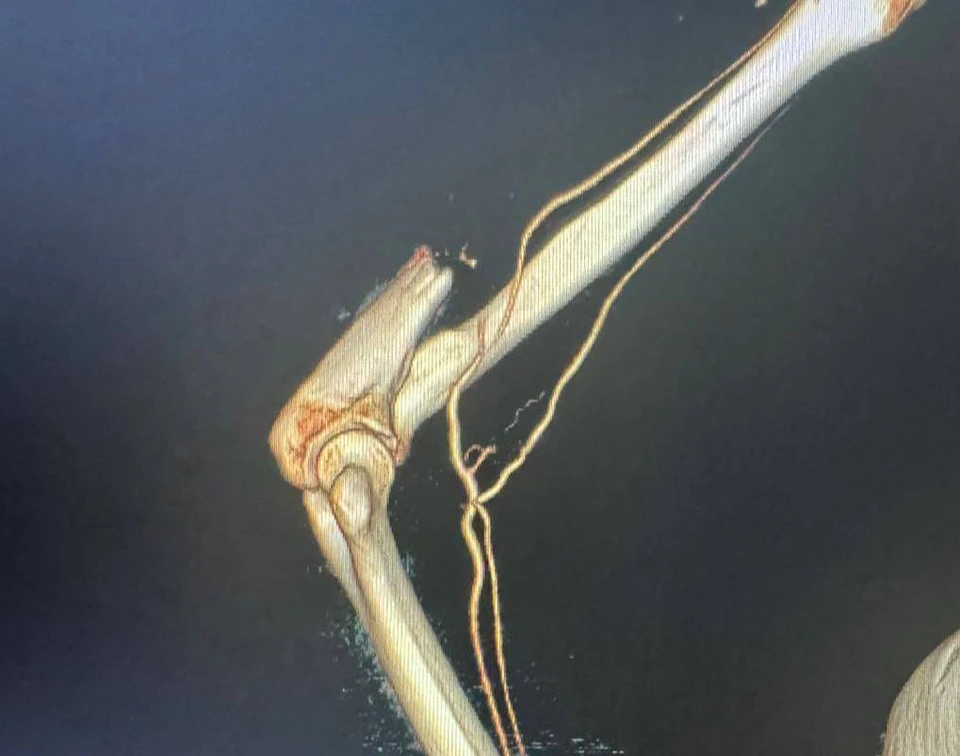

Женщину доставили в Кемерово санавиацией. Уже были признаки нежизнеспособности кисти, но результаты УЗИ сосудов конечности и МСКТ с контрастированием показали, что в пораженной руке все же есть кровоток.

«Врачи в ходе операции освободили сосудистый пучок на кисти в области лучезапястного сустава, и восстановили кровообращение. На следующий день после операции кисть уже была теплой и жизнеспособной», - рассказал Дмитрий Беглов.